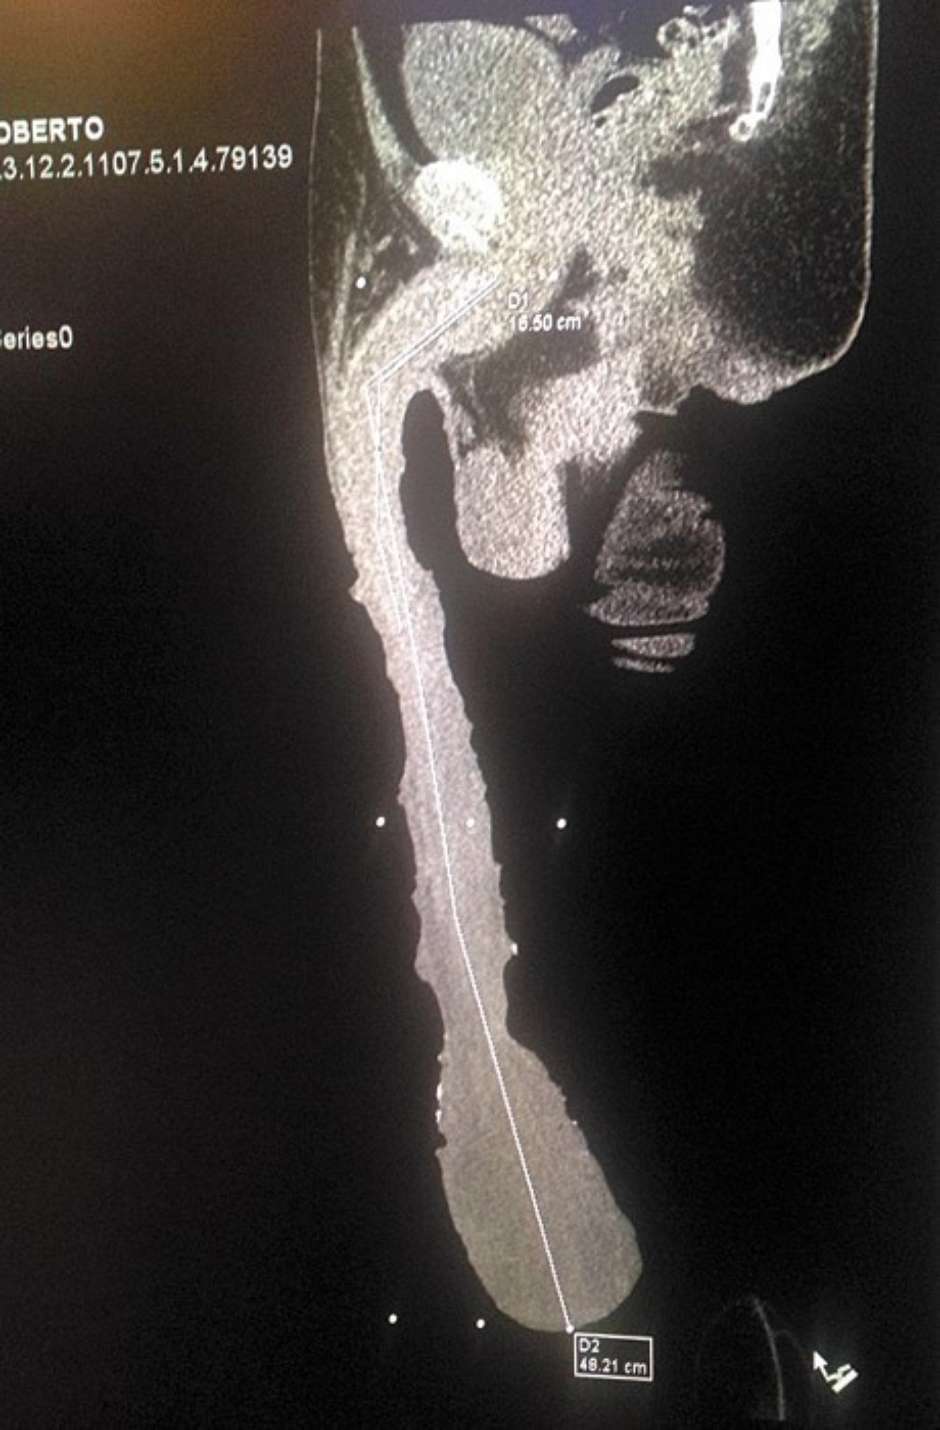

根據外媒綜合報導,2015年卡布瑞拉在網路上上傳了他測量下體的影片,造成國外媒體的轟動,紛紛報導這位有「48公分的男子」,當時他想挑戰金氏世界紀錄但未成功。也被質疑尺寸造假,而根據影像診斷專家穆洛(Jesus Pablo Gil Muro)指出,斷層掃描發現卡布瑞應該只有18公分,而其餘的長度都是包皮、加上皮膚發炎、血管組織,根本無法算入一部分。